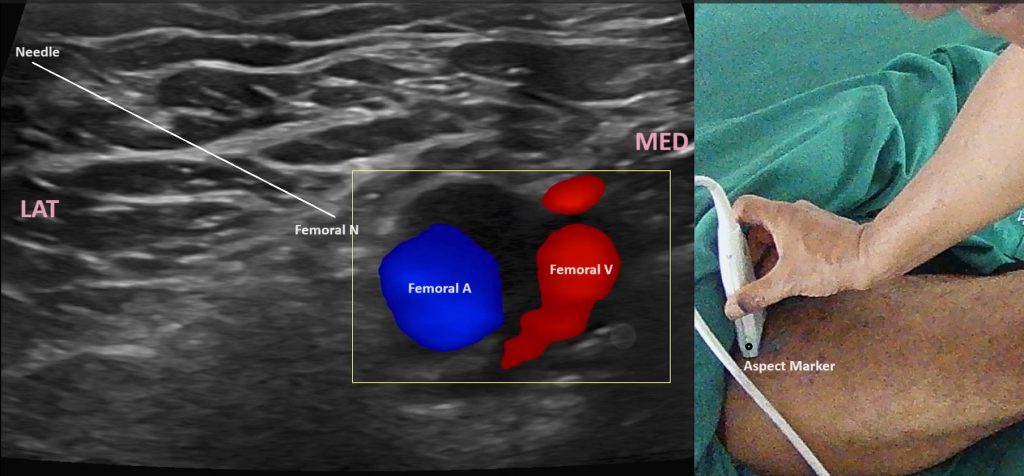

- Probe Placement: Place the ultrasound probe transversely in the inguinal crease to obtain a short-axis view of the femoral nerve.

- Identification of Structures: Identify the femoral artery and vein, with the femoral nerve located lateral to the artery. The nerve typically appears as a hyperechoic (bright) structure.

- Needle Insertion: Using an in-plane technique, insert the needle from lateral to medial. Continuous ultrasound visualization ensures precise needle guidance.

- Confirmation of Needle Placement: The needle tip should be adjacent to the femoral nerve, which can be confirmed by slight movement of the nerve or tissue around it upon needle contact.